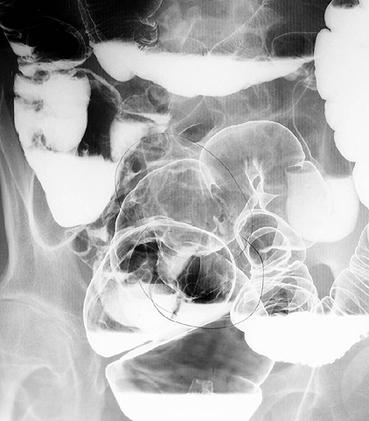

疾病(病理主体)的分类恶性上皮性肿瘤/粘液癌

部位(按器官分)大肠/直肠

检查方法X线

肿瘤的肉眼分类1型(肿瘤型)/

肿瘤最大直径40以上

肿瘤的深度ss(a1)